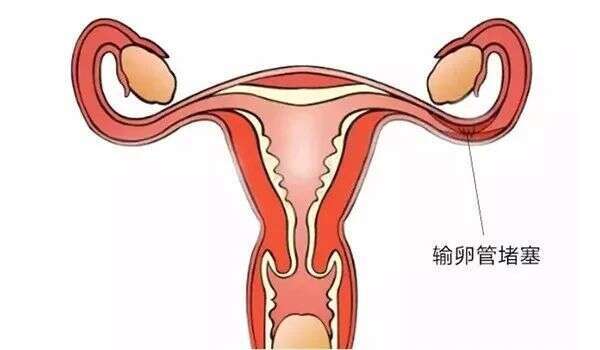

输卵管堵塞是指输卵管内受到阻碍,无法正常传递卵子的情况,这种状况可能会阻碍受孕。据研究表明,有些输卵管的情况下,没有堵塞的现象。比如,根据“生化”这种检查手

出现输卵管堵塞的原因有多种,具体以下几点一起来看看。 ① 出现月经不调 输卵管发生炎症,由炎症引发的堵塞,会对卵巢功能造成损害,从而导致月经不调。 ②

双边输卵管堵塞(bilateraltubalocclusion)是一种常见的不孕症,它是指双侧输卵管有堵塞,卵子不能从卵巢通过输卵管传递到子宫,从而导致不能